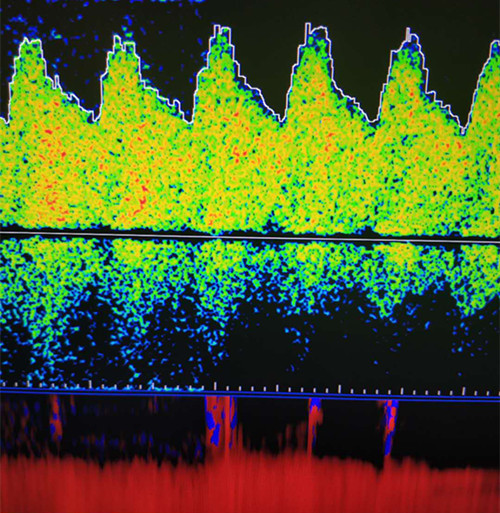

近日,一名中年女性在我院功能科進(jìn)行經(jīng)顱多普勒(TCD)體檢時(shí),主檢醫(yī)師發(fā)現(xiàn)該女性后循環(huán)動(dòng)脈血流速度異常增高,前循環(huán)動(dòng)脈呈相對(duì)低波動(dòng)改變,雙側(cè)壓頸試驗(yàn)陰性。這種異常的顱內(nèi)動(dòng)脈改變引起了主檢醫(yī)師的關(guān)注,遂請(qǐng)科里高年資醫(yī)師進(jìn)行進(jìn)一步詳細(xì)檢查。經(jīng)過(guò)詢問(wèn)病史,并結(jié)合TCD檢查結(jié)果和頸動(dòng)脈超聲觀察,最終診斷為煙霧病。

前循環(huán)動(dòng)脈低波動(dòng)表現(xiàn)